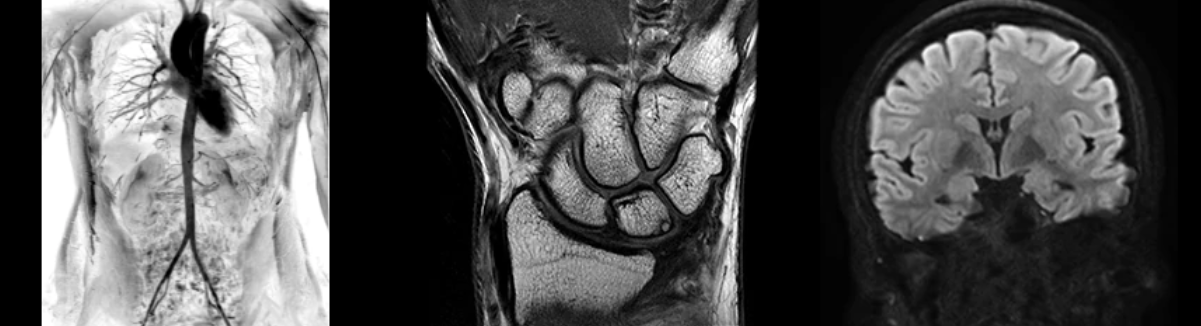

SIGNA Premier — система нового поколения для МРТ с широкой апертурой гентри от компания GE Healthcare и первый в области аппарат со 146-канальной РЧ-катушкой.

Инновационная технология AIR

Революционная конструкция катушки, которая комфортно прилегает к телу пациента. Легкое позиционирование — для максимального качества изображения.

Радиочастотная технология SIGNA Premier разработана для обеспечения большей клинической производительности и высокого качества изображения, особенно для приложений, требующих большого количества данных, на основе архитектуры Total Digital Imaging (TDI). 146 независимых каналов позволяют одновременно сочетать несколько поверхностных катушек со сверхвысоким количеством каналов для более быстрых ускорений и бескомпромиссной четкости изображения.

• NeuroWorks

Представляет собой универсальное решение для визуализации анатомии головного мозга, позвоночника, сосудов и периферических нервов с четкой дифференциацией тканей.

• OrthoWorks

Программное решение OrthoWorks разработано для визуализации структур опорно-двигательного аппарата с прекрасным контрастированием тканей.

• BodyWorks

Используйте BodyWorks для визуализации абдоминальной и тазовой областей с учетом любых типов пациентов.

• OncoWorks

Включает клинические приложения для обработки и визуализации анатомических и морфологических данных, специфичных для каждого типа онкологических образований.

•  CVWorks

Приложение для кардиовизуализации, с помощью которого вы сможете получить данные о морфологии, динамике кровотока, функции миокарда, а также информацию о структуре сосудов.

• PaedWorks

Набор специализированных протоколов, позволяющих без усилий удовлетворять потребностям самых маленьких и уязвимых пациентов.